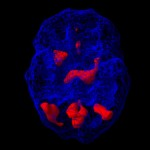

Brain map običajno pokaže povišano aktivnost v limbičnem predelu, med počitkom in koncentracijo. V limbičnem predelu se generirajo čustva, kontrolira se kako smo srečni ali nesrečni. Depresija je tesno povezana z limbičnim predelom. Zmanjšana je aktivnost v prefrontalnem predelu, v cerebellumu in bazalnih ganglijih.

Brain map tega podtipa pokaže povišano aktivnost v stanju relaksacije, kot pri koncentraciji v predelu cingulate gyrus, ter zmanjšano aktivnost v prefrontalnem korteksu, bazalnih ganglijih in cerebellumu.